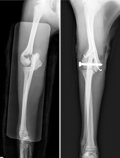

獣医のカルテ